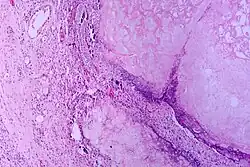

Pancreatic Ductal Adenocarcinoma (PDAC) is one of the most lethal cancers and has an expected survival of five years.[11] Pancreatic adenocarcinoma cells resemble pancreatic ductal cells. Both cell groups show tubule formation, cuboidal shape, and ductal markers. Additionally, acinar and endocrine cells have often been found in many of these cancers, demonstrating plasticity and the possibility that the initial target cells are pancreas progenitor cells.[3] Moreover, human tumors usually go with lower-grade lesions that are called pancreatic intraepithelial neoplasias (PanINs) and are in ducts. Because these lesions are in ducts, this means that it is possible that the beginning target cells are ductal cells.

- ^ "cross section: human pancreas". Berkshire Community College Bioscience Image Library. 2019-04-18. Retrieved 2022-12-07.